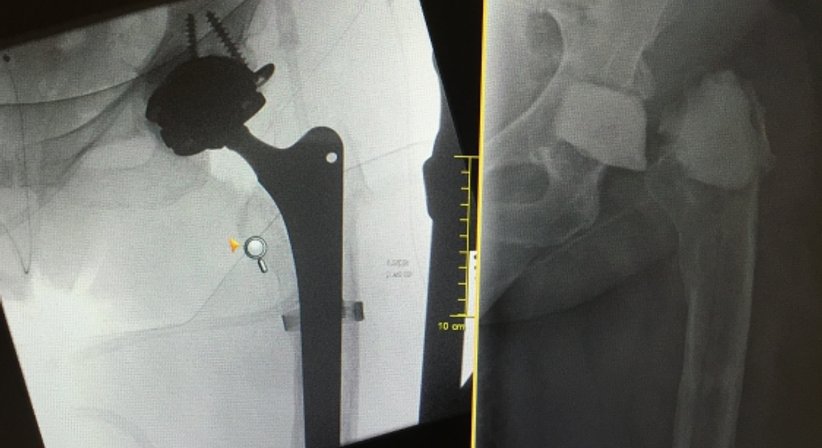

Ist die Entscheidung für einen Austausch des künstlichen Gelenkes gefallen, gilt es, das Operationsverfahren festzulegen. Es ergibt sich z. B. aus der Art der Lockerung, dem Zustand der umgebenden Knochen- und Weichteilstrukturen, den Funktionszielen durch den Eingriff (z. B. Sportfähigkeit), dem Allgemeinzustand des Patienten, bei einer Infektion nach deren Dauer und dem Keimtyp.

Der Austausch der Hüftprothese oder Knieprothese ist aufwändiger und anspruchsvoller als ihre Erstimplantation.

Es kommen Prothesen zur Anwendung die speziell für diese Situation geeignet sind.